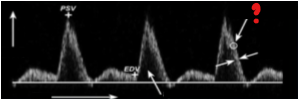

What represents the question mark on this image?

Time